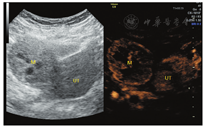

患者女,34岁,于顺产后43 d检查发现右侧卵巢囊实性肿块入院治疗。既往体健,生育史:孕4产2,曾流产2次。妇科查体:子宫正常大小,活动可,于右侧附件区可扪及一直径约5 cm肿块,活动可,界清,无明显压痛,左侧附件区未扪及明显肿块。辅助检查:CEA、CA199、CA125、AFP、卵巢癌相关抗原均为阴性。经阴道超声示:子宫体积正常(三径和约142 mm,宫颈厚28 mm,内膜厚约5.0 mm),宫壁未见明显肿块占位;右侧卵巢体积大、内可见一大小约49 mm×41 mm×39 mm的囊实性肿块,肿块边界清楚,形态规则,内部回声不均匀,可见多个囊性无回声区(较大者约13 mm×11 mm)(图1),能量多普勒示肿块内部及周边可见点条状血流信号(图2),脉冲多普勒(PW)示最高流速(Vmax)0.18 m/s,最低流速(Vmin)0.09 m/s,阻力指数(RI)0.50;子宫及左侧附件区未见明显异常回声。超声提示:①右侧卵巢内囊实性肿块;②子宫及左侧卵巢未见明显异常。进一步行超声造影成像示:增强早期时,右侧卵巢内肿块周边呈环状高增强,并早于子宫肌层增强(图3);内部实性部分呈不均匀等增强,并与子宫肌层同步增强;内部囊性部分无增强(图4)。造影剂消退时,肿块内部早于子宫肌层消退,而周边仍呈环状增强(图5),超声造影提示右卵巢肿块血供较丰富,表现"快进快退"。磁共振增强扫描提示:子宫右上方占位,考虑来源右卵巢性索间质肿瘤-颗粒细胞瘤可能,其他待排。术前拟诊"盆腔肿块性质待查",予行腹腔镜下右侧附件切除术,术中所见:右侧卵巢内见一肿瘤,直径约5 cm,呈囊实性,表面包膜完整,右侧输卵管攀附其上,外观正常;子宫正常大小,左侧卵巢及输卵管外观正常。术后病理镜下见肿瘤细胞弥漫性增生,呈片状、条索状,灶性腺样结构,部分区域可见大小不等的囊腔,核大小较一致,圆形或椭圆形,核仁可见,核分裂象约1~2个/10HPF,间质纤维组织及厚壁血管增生,黏液样变、灶性出血。免疫组化结果显示:Vimentin(+),CD10(+),ER(-),PR(-),CD34(血管+),EMA(-),P53(散在弱+),Ki67(灶性15%+)(图6)。结合免疫组化考虑卵巢性索-间质肿瘤,倾向卵巢间质瘤,送至复旦大学妇产医院会诊,诊断为右侧卵巢微囊性间质瘤。

卵巢MCST形态学表现上有完整的包膜,且实性肿块内部有特征性的微囊结构,这些在二维超声图像上有相应的表现,如本例患者卵巢MCST经阴道超声表现为卵巢内囊实性肿块,肿块边缘可见少量正常卵巢组织并与卵巢界线清楚,肿块边界清楚,形态规则,中央部可见多个规则的囊性无回声区(长径约10 mm)、透声好。彩色血流示肿块周边可见半环形血流信号,内部可见少许点状血流信号显示,频谱多谱勒显示为中等阻力。超声造影增强早期表现为包膜最先呈环状高增强(始增时间早于宫体),内部与宫体同步等增强,并由周围向中心增强,消退期表现为内部早于子宫肌层消退,而包膜仍呈环状持续高增强。